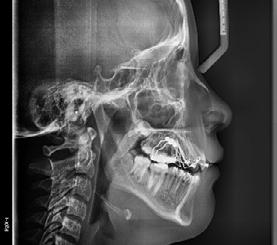

En la lateral de cráneo (Figura 4) se ve la clase III esquelética, con patrón de crecimiento hiperdivergente, los incisivos superiores proinclinados e inferiores retroinclinados y las vías aéreas permeables.

En la radiografía panorámica (Figura 5) se observan 28 dientes permanentes presentes, con tratamiento de conductos en el OD 36.

Figura 4. Rx Lateral de cráneo. Figura 5. Rx panorámica.